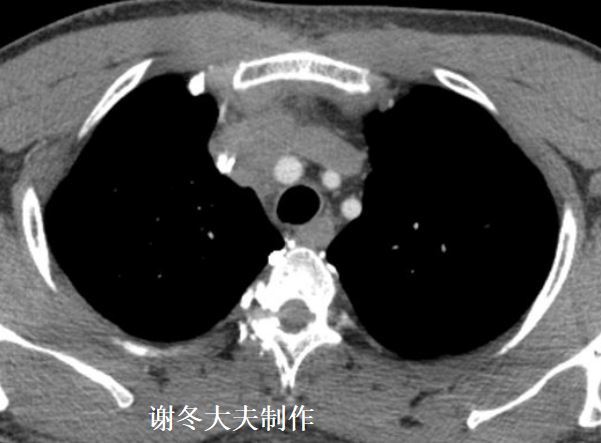

7.谢大夫,这个纵隔占位,是胸腺瘤吗?

回答:这是一个支气管囊肿,不是胸腺瘤,但有时候纵隔囊肿包括,胸腺囊肿,支气管囊肿,心包囊肿,术前很难鉴别诊断,有时即使CT结合磁共振也难以诊断。胸腺瘤往往也会合并胸腺囊肿,因此有时对于胸腺瘤和纵隔囊肿无法鉴别的情况下,必要时还是需要手术探查,依靠病理最终诊断。